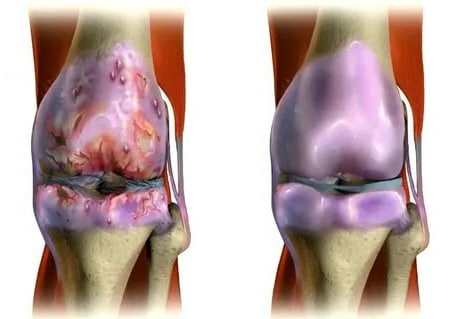

Марія: "Секрет полягає в розумінні причини хвороби. Ніхто не знає цього, тому що люди не хочуть бачити істину. Загалом в енциклопедіях налічують до 147 можливих причин розвитку суглобових патологій, але сучасні дослідження знайшли ключову - СУГЛОБИ РУЙНУЮТЬСЯ ЧЕРЕЗ ПОГІРШЕННЯ КРОВОПОСТАЧАННЯ, ЗВІДТИ І БІЛЬ через погане живлення й дегенерацію тканин.

Так розвиваються недуги суглобів: від "невинних" болю й дискомфорту до повної неспроможності рухатися

Суглобові патології - небезпечні та підступні хвороби, що призводять до передчасної втрати здатності рухатися аж до повного знерухомлення й інвалідності.

При неправильному харчуванні, постійних навантаженнях, браку сну й стресах кровоносні судини дуже швидко слабшають і руйнуються, що призводить до погіршення живлення тканин, а потім до стрімкого розвитку серйозних патологій і ускладнень.